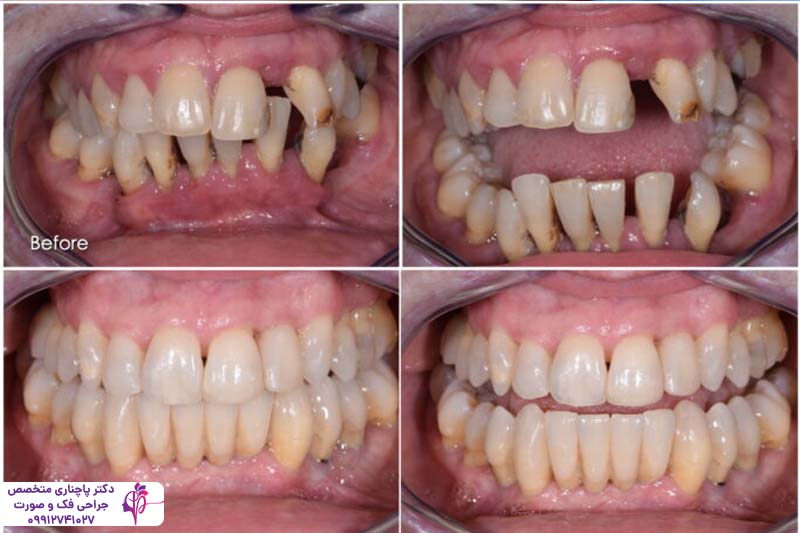

درمان بیماریهای لثه قبل از ایمپلنت یکی از مهمترین مراحلی است که باید انجام شود. بیماریهای لثه در صورت عدم درمان میتوانند تاثیر مستقیم روی موفقیت کاشت ایمپلنت داشته باشند. در دنیای دندانپزشکی مدرن ایمپلنت دندان به عنوان یکی از پیشرفتهترین روشها برای جایگزینی دندانهای از دست رفته به شمار میرود. این روش هم ظاهر طبیعی را به دندانها برمیگرداند هم عملکرد فک را هنگام جویدن و صحبت کردن بهبود میبخشد. اما موفقیت کاشت ایمپلنت به عوامل مختلفی بستگی دارد و مهمترین آنها سلامت لثههاست. درمان بیماریهای لثه قبل از ایمپلنت اهمیت زیادی دارد چون وجود هر گونه عفونت یا التهاب در لثه میتواند باعث شکست کاشت ایمپلنت شود.

بسیاری از افراد به دلیل از دست دادن دندانها به دلایل مختلف به بیماریهای لثه دچار میشوند. و این بیماریها بزرگترین مانع برای کاشت ایمپلنت هستند. در این مقاله قصد داریم درباره درمان تحلیل لثه بعد از ایمپلنت، ایمپلنت لثه تحلیل رفته، دلایل تحلیل لثه بعد از ایمپلنت و نکات مهم در این زمینه بپردازیم. ادامه این مقاله را با ما دنبال کنید.

روش های ترمیم و درمان بیماریهای لثه قبل از ایمپلنت

روشهای مختلفی برای ترمیم و درمان بیماریهای لثه قبل از ایمپلنت وجود دارد که بسته به شدت بیماری انتخاب میشوند. یکی از رایجترین روشها، تمیز کردن عمیق دندانهاست که شامل اسکالینگ و روت پلنینگ میشود، در این روش پلاک و جرم را از زیر خط لثه برمیدارند تا عفونت کنترل شود. در بعضی موارد پیشرفته و حاد بنا به تشخیص و صلاحدید دندان پزشک جارحی انجام میشود. جراحی فلپ یکی از این روشهای جراحی است که در آن بافت لثه را بلند میکنند تا با دسترسی راحتتر به ریشهها بافت آسیبدیده را بردارند. استفاده از آنتیبیوتیک هم میتواند میزان باکتریها را کم کند.

یکی دیگر از روشهای درمان بیماریهای لثه قبل از ایمپلنت روش گرافت لثه است. در این روش بافت سالم را از جای دیگری برمیدارند و به لثه آسیبدیده پیوند میزنند. لیزر درمانی نیز یک گزینه مدرن است. در این روش به کمک پرتوهای لیزر با دقت بالا باکتریها را از بین میبرند و در نتیجه التهاب کمتر میشود بدون اینکه نیازی به برش دادن لثه باشد. این روش نه تنها به درمان بیماریهای لثه قبل از ایمپلنت کمک میکند بلکه برای حفظ بهداشت دهان و دندان هم موثر است.

تحلیل لثه پس از کاشت ایمپلنت میتواند مشکلساز باشد. این مشکل اغلب به دلیل التهاب یا بیماریهای لثهای مانند پریایمپلنتیت رخ میدهد که باکتریها به بافت اطراف ایمپلنت نفوذ کرده و باعث عقبنشینی لثه میشوند. برای درمان تمیز کردن عمیق برای حذف پلاک و جرم، استفاده از آنتیبیوتیکها در موارد عفونی، و در شرایط پیشرفتهتر، جراحی لثه یا گرافت لثه برای بازسازی بافت از دست رفته پیشنهاد میشود. در موارد حادی که استخوان فک زیادی تحلیل رفته و تراکم لازم را ندارد باید پیوند استخوان فک از لگن انجام شود تا بستر مناسب برای کاشت ایمپلنت فراهم شود.رعایت بهداشت دهان، از جمله مسواک زدن منظم و استفاده از دهانشویه ضدباکتری، همراه با ویزیتهای دورهای دندانپزشکی کمک میکند تا جلوی پیشرفت تحلیل لثه را بگیرید و سلامت ایمپلنت را حفظ کنید.